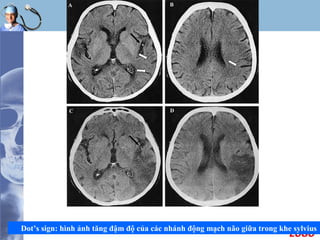

Tìm dấu hiệu huyết khối trong lòng mạch

 Dấu hiệu tăng đậm độ của động mạch do huyết khối

trong lòng mạch máu, gặp tại :

- Động mạch não giữa và các nhánh ( Dot sign )

- Nơi tận cùng động mạch cảnh trong

- Động mạch thân nền

 Ðây là một triệu chứng tiên lượng nặng vì vùng nhồi

máu lớn

 Tuy nhiên cần lưu ý trong trường hợp triệu chứng xuất

hiện đối xứng hai bên ( vôi hóa ), bên có huyết khối

phải tăng quang nhiều hơn.

LOGO

Dot’s sign: hình ảnh tăng đậm độ của các nhánh động mạch não giữa trong khe sylvius